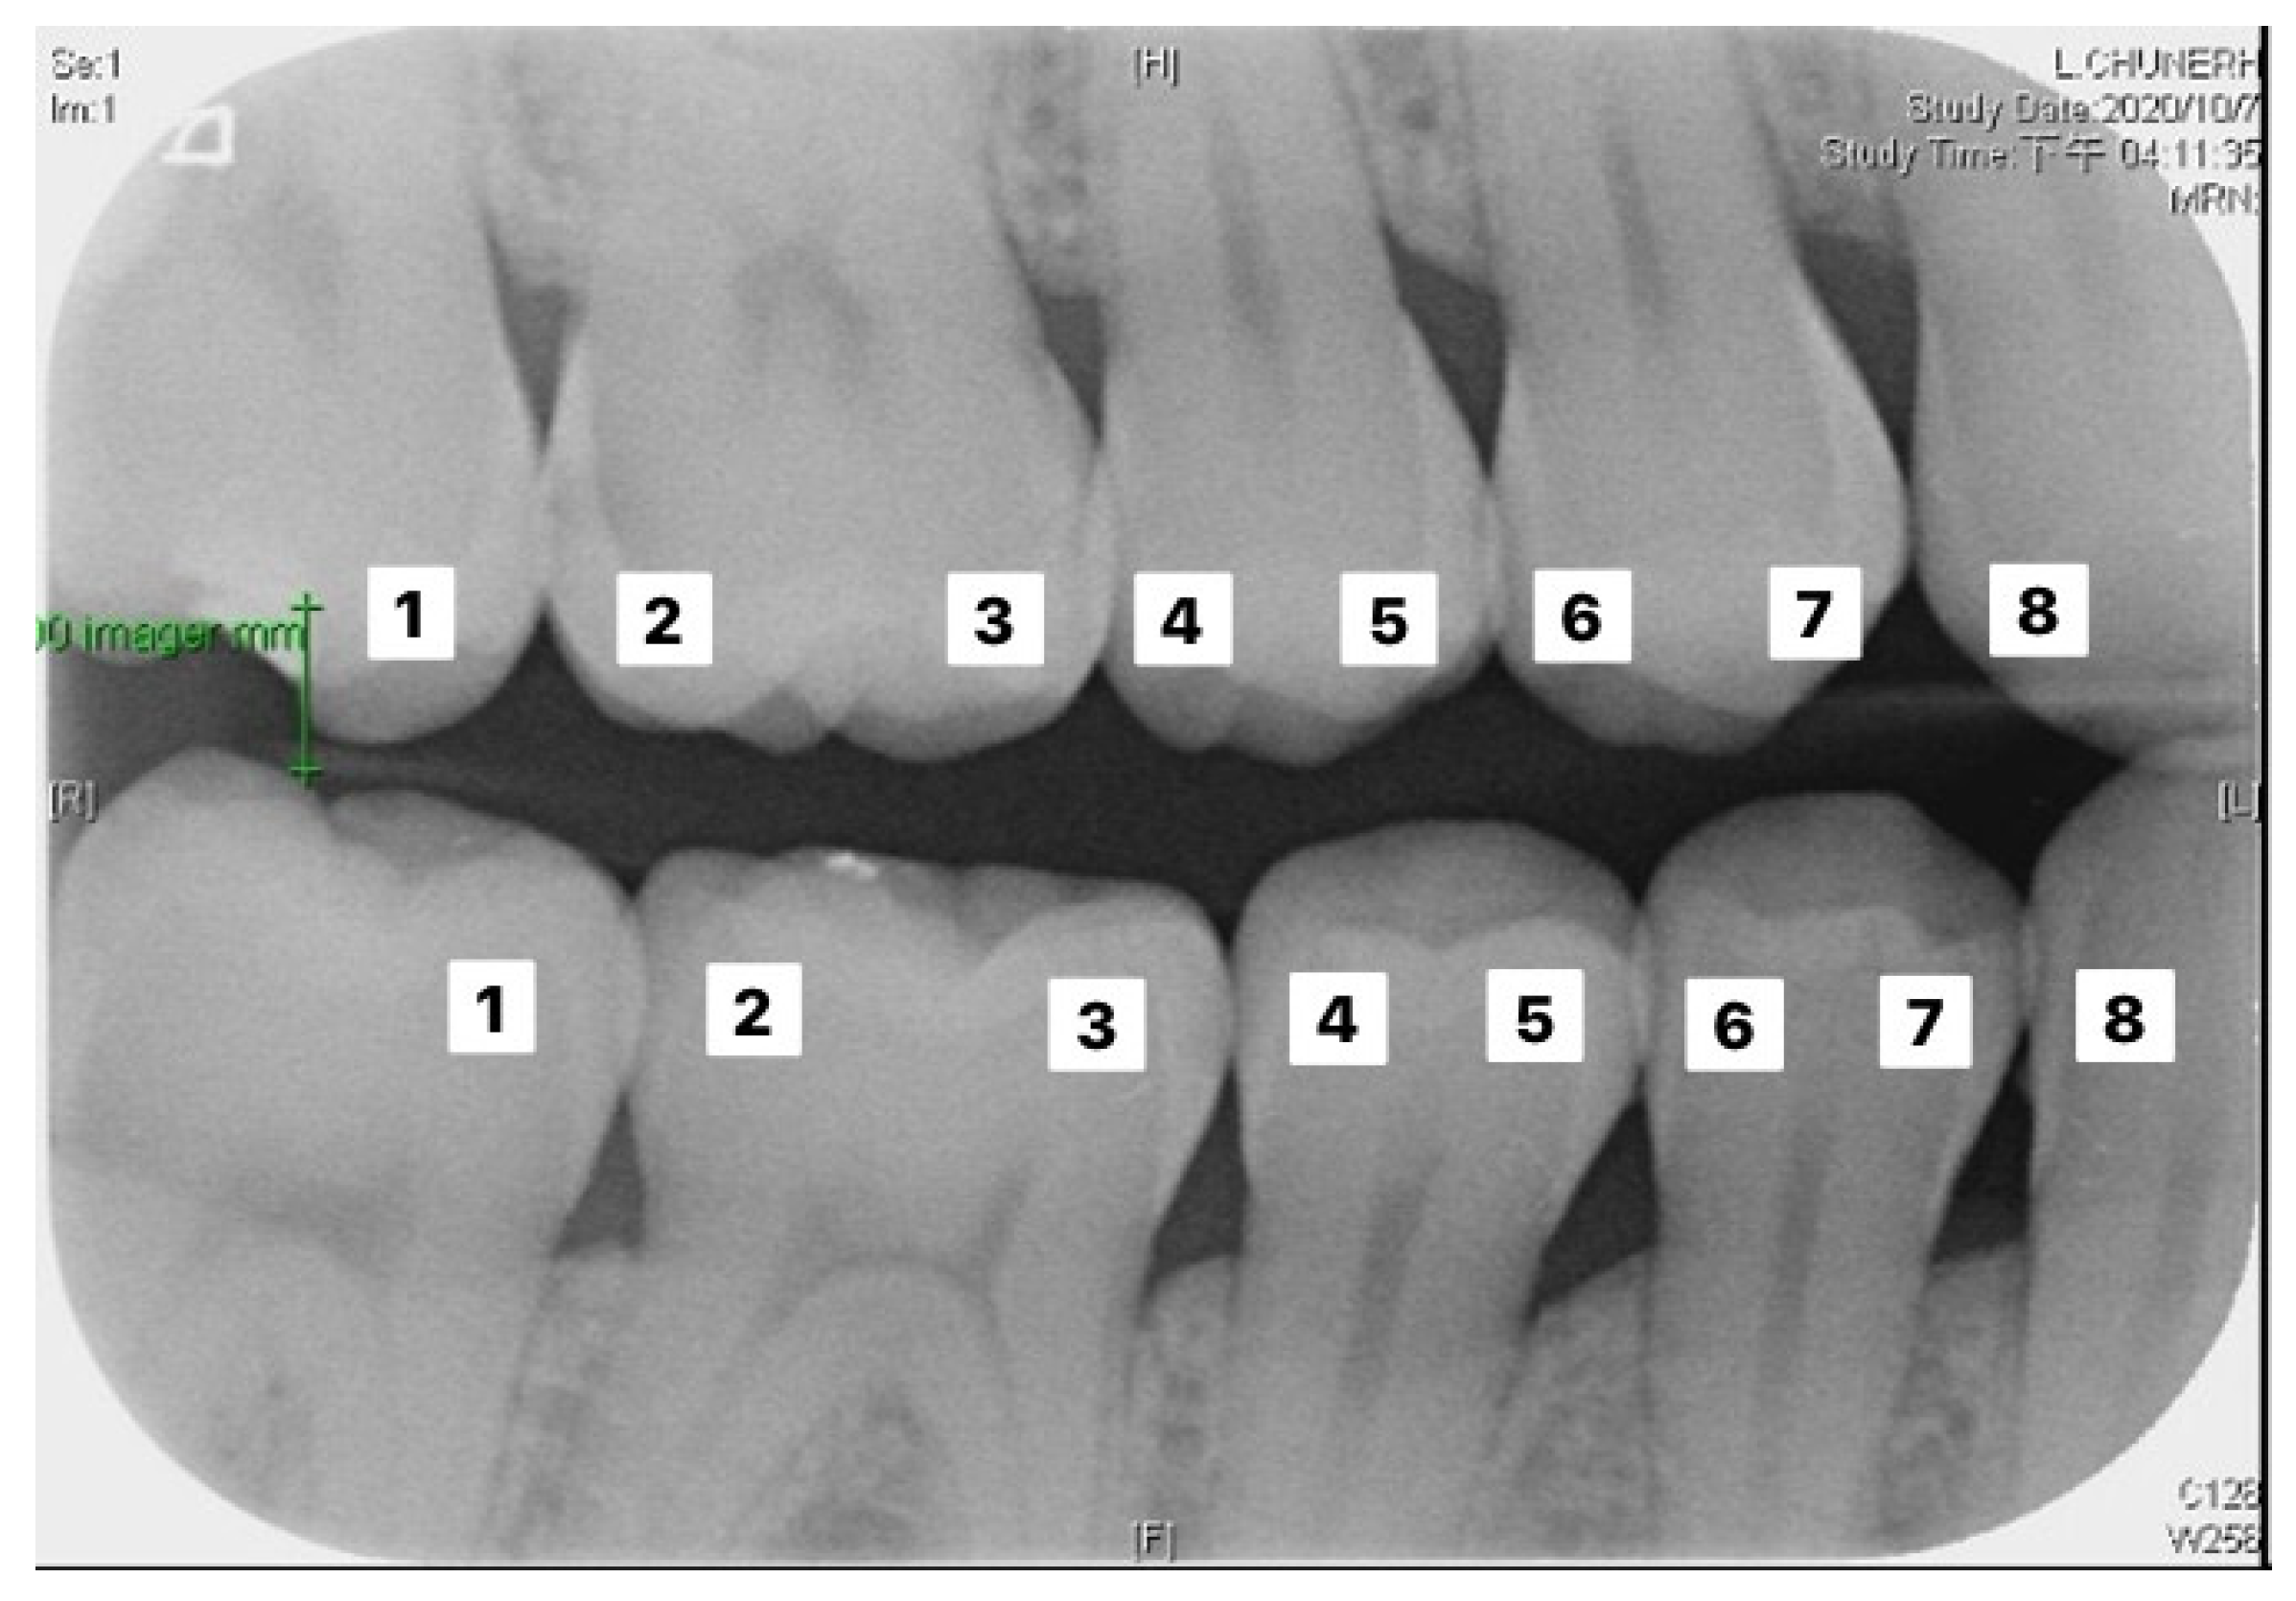

Figure 9.

Image example of outer teeth for validation (from left to right, in order of 1–8).

Table 6 and Table 7 correspond to the judgment of the upper and lower rows of teeth in Figure 10. Results show that the accuracy of the proposed model for judging the restorations was 95.56%, which is an improvement compared to Lin et al. [30], with an accuracy of 90.23%. The proposed method in Lin et al. [30] first enhanced the classification features of the image, and then added the regular term and impulse, before establishing a CNN model with the ReLU function. With regard to judging caries, the proposed model in this study showed an accuracy of 90.30%, which was also an improvement compared to Singh and Sehgal [31], with an accuracy of 80.00%, which used a neural network classifier to classify caries. Table 8 and Table 9 are the truth tables of different CNN models.

Figure 10.